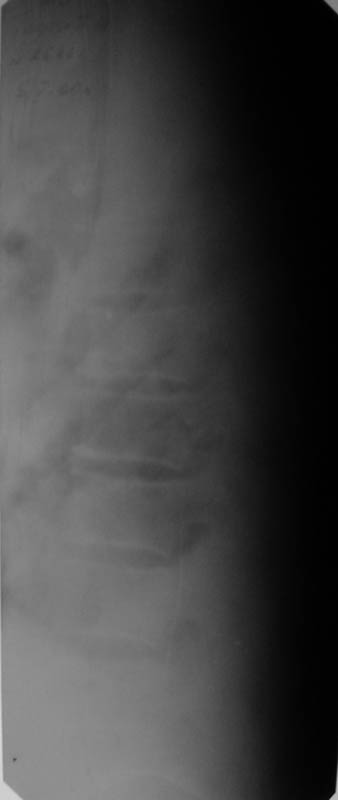

Мужчина, 48 лет. 8.04. 2000 г. - сочетанная травма: компрессионные переломы тел Th4- Тh6 и L1 позвонков с синдромом полного нарушения проводимости спинного мозга -

нижней параплегией, нарушением чувствительности и функции тазовых органов; переломы III-IV ребер справа,VI-VII ребер слева со смещением,травматический немопневмоторакс слева, гемоторакс справа, оскольчатые переломы обеих лопаток со смещением, перелом правой ключицы со смещением, тупая травма живота, ушиб сердца. Осложнения:посттравматическая пневмония, посттравматический плексит справа, цистит, пролежень в области крестца.

В настоящее время жалобы на отсутствие чувствительности в нижних конечностях, невозможность самостоятельной ходьбы (передвигается на кресле).КОНСУЛЬТАТИВНОЕ ЗАКЛЮЧЕНИЕ ЯМР-ТОМОГРАФИЧЕСКОГО ИССЛЕДОВАНИЯПроведена МР_томография грудного отдела позвоночника в сагиттальной проекции, с различной степенью контрастирования тканей, в режимах Т1 и Т2 В/И + МР-миелоурография. Визуализированы: спинной мозг с уровня D1 до уровня D12, тела позвонков D1-D12, межпозвонковые диски. Спинной мозг на уровне D4-D6 истончен с неровными нечеткими контурами, гетерогенной структуры, умеренно пониженной интенсивности на Т1 В/И, без очаговых изменений. Отмечается клиновидная деформация тела D5, снижена высота тела D4, структура его гетерогенная. Обращают внимание выраженные дегенеративные изменения дисков в грудном отделе позвоночника: снижение их высоты, изменение структуры изображения за счет исчезновения высокоинтенсивного сигнала от ядер. При исследовании в режиме МР-миелоурографии ликворный сигнал на уровне D4-D5 почти прерывается, интенсивность его существенно снижена.

ЗАКЛЮЧЕНИЕ: ПОСЛЕДСТВИЯ КОМПРЕССИОННОГО ПЕРЕЛОМА ТЕЛА D4-D5 С КОМПРЕССИЕЙ СПИННОГО МОЗГА. МРТ-ПРИЗНАКИ МИЕЛОПАТИИ И РУБЦОВО-СПАЕЧНОГО ПРОЦЕССА В ПОЗВОНОЧНОМ КАНАЛЕ НА УРОВНЕ D4-D5. ВЫРАЖЕННЫЕ ДЕГЕРАТИВНЫЕ ИЗМЕНЕНИЯ ДИСКОВ В ГРУДНОМ ОТДЕЛЕ ПОЗВОНОЧНИКА.